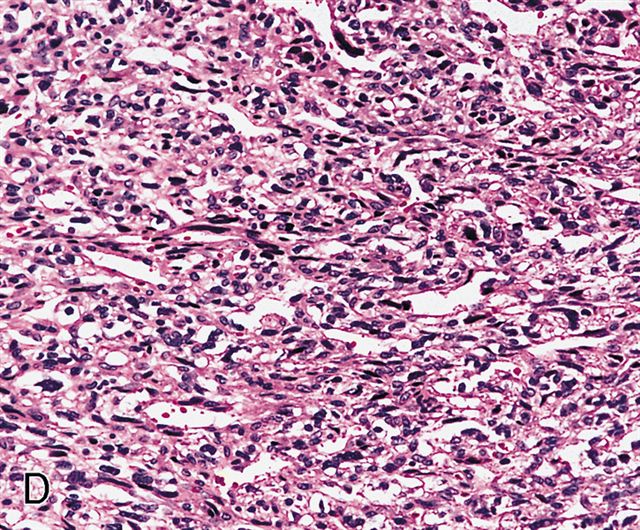

Microscopic (histologic) description

- Sheets of large, atypical and frequently multinucleated polygonal, spindled or rhabdoid eosinophilic cells (Am J Surg Pathol 2009;33:1850)

- Cross striations are seldom detected

Microscopic (histologic) images